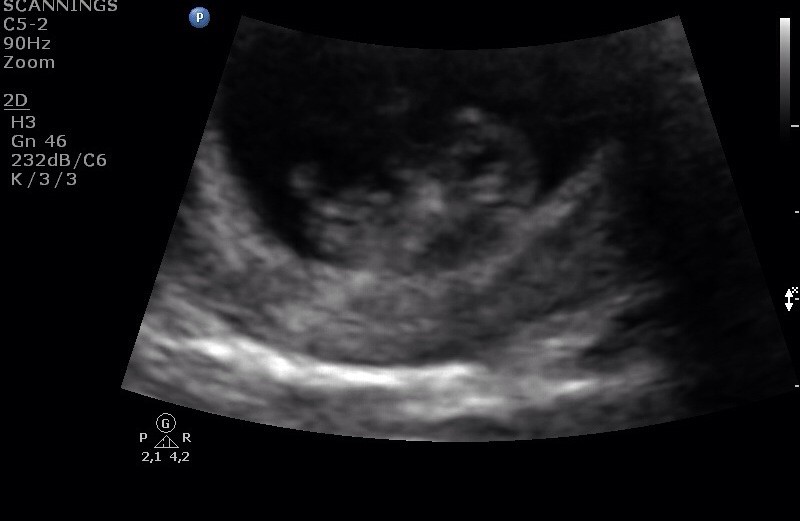

Dette er fra privat tryghedsscanning da jeg var (scannet til at være)9+3 eller sådan noget. Man kunne tydeligt se bevægelser samt at hun prøvede at nå fødderne. Så vildt

Vedhæftede fotos (klik for at se i fuld størrelse)